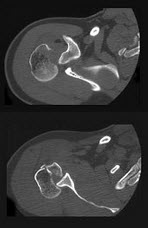

79、单项选择题

男,45岁,车祸后左膝部剧痛,活动受限2小时,结合影像学检查,最可能的诊断是()

A.股骨颈骨折

B.股骨下端骨折

C.柯莱斯骨折

D.胫骨骨折

E.腓骨骨折